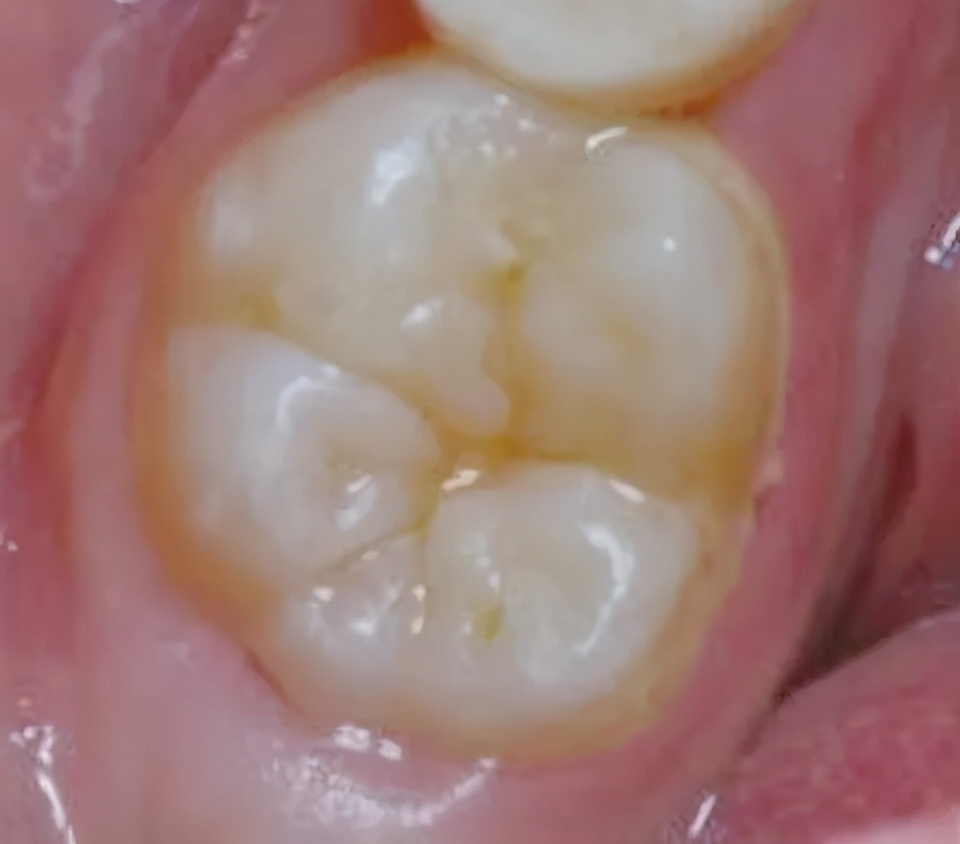

窝沟是磨牙(即后槽牙)咀嚼面上的凹坑和裂隙,凹陷处容易填满食物残渣,又不容易被刷干净

窝沟封闭,就是把一种对人体无害的合成有机高分子树脂材料,涂在牙齿的深窝沟内。材料凝固后,可以长期保留在窝沟中,如同形成一层保护性的屏障,隔绝了细菌和食物残渣对牙齿的侵蚀。

简单讲就是给牙齿“填坑”。

这张图就是给牙齿“填坑”的详细步骤